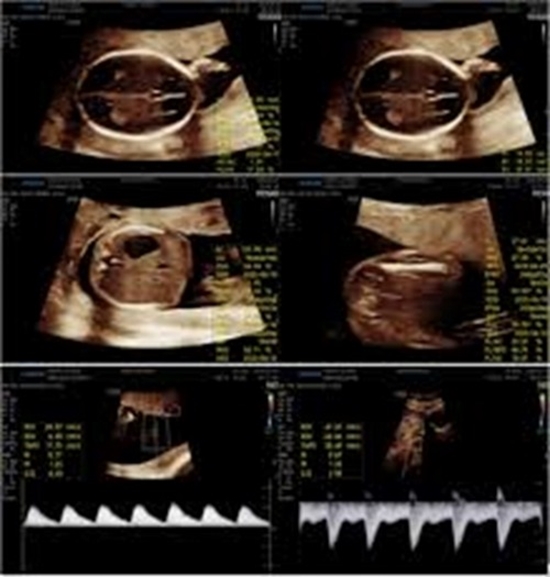

Materials and methods: This cross-sectional study included 300 healthy pregnant women with gestational ages between 18 and 22 weeks, determined by last menstrual period or first-trimester ultrasound. Participants underwent routine biometric ultrasound assessments, including biparietal diameter (BPD), head circumference (HC), abdominal circumference (AC), femur length (FL), estimated fetal weight (EFW), and Doppler evaluations of the umbilical and uterine arteries. PT was measured perpendicularly to the uterine wall at the site of cord insertion. Statistical analyses included descriptive statistics, Pearson correlation coefficients, and independent t-tests, with statistical significance set at p < 0.001.

Results: The mean placental thickness (PT) was 23.45 ± 3.99 mm. Statistically significant (p < 0.001) but weak positive correlations were observed between PT and the following fetal growth parameters: estimated fetal weight (EFW) (r = 0.29), abdominal circumference (AC) (r = 0.33), head circumference (HC) (r = 0.21), biparietal diameter (BPD) (r = 0.27), and femur length (FL) (r = 0.29). Gestational age showed a weak positive correlation with PT (r = 0.32). Correlations between PT and Doppler indices, including the umbilical artery pulsatility index (PI) and uterine artery PI, were trivial (r = -0.16 and r = 0.06, respectively). No significant differences in PT were observed based on fetal gender.